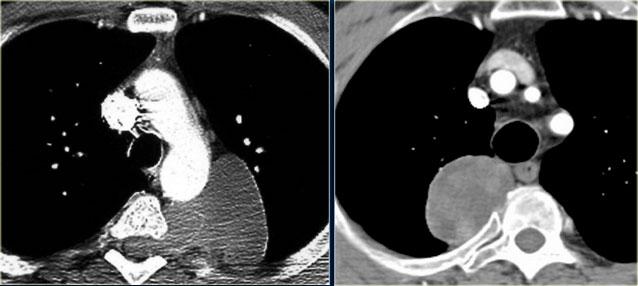

Phim ngực cho thấy các đặc điểm điển hình của u lympho Hodgkin, ví dụ: một khối trung thất trước.

Các hình ảnh CT của cùng bệnh nhân cho thấy một khối mô mềm lớn ở trung thất trước, xuất phát từ tuyến ức.

Có hạch cạnh khí quản kèm theo (mũi tên).

Hai trường hợp u lympho Hodgkin khác.

Các trường hợp này cũng cho thấy khối trung thất trước và hạch cạnh khí quản to.